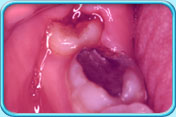

Food debris and bacteria are easily trapped in the space between the crown of the wisdom tooth and the overlying gingiva (gum), resulting in the infection of the surrounding tissues (Pericoronitis). Furthermore, the infected, swollen overlying gingiva is easily hurt by the opposing upper tooth making it difficult to recover.

Pericoronitis has the following signs and symptoms:

Pain and swelling of the cheek.